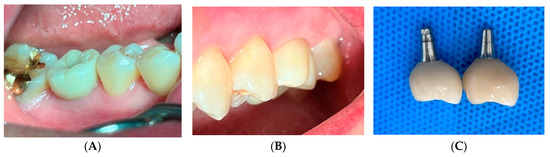

Prosthetic Management of Peri-Implant Mucositis via CRD Optimization: A Split-Mouth Case Report

Background: Subcrestally placed implants (SPIs) present advantages for bone preservation and soft tissue support but pose challenges in maintaining peri-implant soft tissue health. This case explores the role of Crest to Restoration Distance (CRD) in the development and resolution of peri-implant mucositis. Case [...] Read more.

Background: Subcrestally placed implants (SPIs) present advantages for bone preservation and soft tissue support but pose challenges in maintaining peri-implant soft tissue health. This case explores the role of Crest to Restoration Distance (CRD) in the development and resolution of peri-implant mucositis. Case Presentation: A 57-year-old woman received two SPIs—one in the upper left and one in the lower right first molar region. Despite similar implant systems and prosthetic protocols, the upper left implant developed mucositis, characterized by bleeding on probing and discomfort, while the lower right implant remained stable. Three-dimensional analysis using cone-beam computed tomography (CBCT) revealed excessive CRD at the affected site. Results: After prosthodontic revision to reduce the CRD, clinical signs of mucositis resolved, with probing depths reduced to less than 1 mm and no bleeding on probing. The control site remained healthy throughout the observation period. Practical Implications: This case highlights CRD as a modifiable prosthetic factor influencing soft tissue stability. A three-zone model—comprising the sulcus, transitional zone (TZ), and subcrestal zone (SZ)—is introduced to provide a biologically grounded framework for understanding soft tissue adaptation around SPIs. Full article